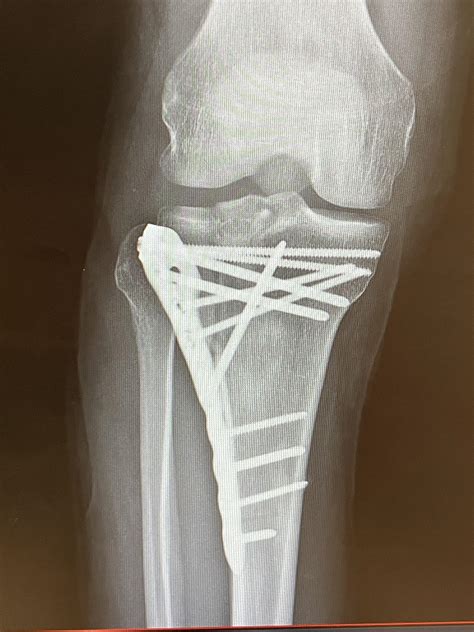

Most significant fractures require surgery to realign the bone fragments and restore the smooth surface of the knee joint. Surgeons often use hardware—such as plates and screws—to hold the bone fragments in the correct position until they knit back together.

Key goals of surgical treatment include:

• Restoring the anatomical alignment of the joint surface.

• Stabilizing the fracture to allow for early movement.

• Preventing long-term complications like post-traumatic arthritis.